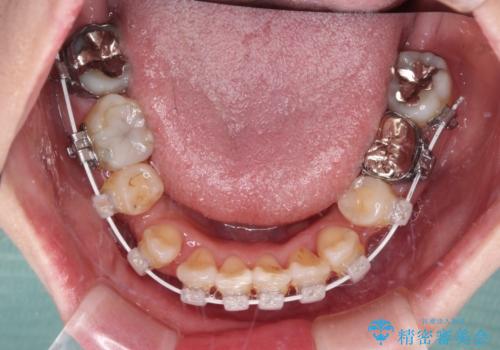

- 矯正装置

- インビザライン・審美装置

マウスピース(インビザライン)はほとんど使用することができませんでしたが、補助装置により上顎の八重歯は改善しておいたので、ワイヤー装置ではスムーズに治療を終えることができました。